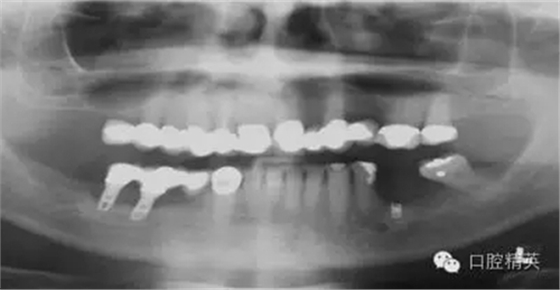

圖2a:術(shù)后曲面斷層片顯示兩顆種植體分別異位于左右側(cè)上頜竇中